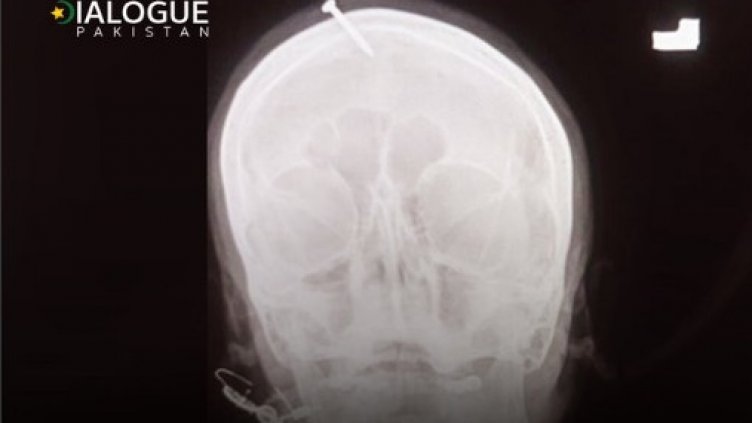

Жената пристигнала в болница в северозападния град Пешавар, след като се опитала сама да извади пирона с клещи, разказва пред АФП лекарят Хайдер Хан. “Тя беше в пълно съзнание, но изпитваше огромна болка“, казва Хан, който отстранил пирона. Майката на три дъщери информирала, че е бременна с друго момиче, добави лекарят. Рентгеновата снимка показала, че петсантиметровият пирон е пробил горната част на челото на жената, но е пропуснал мозъка ѝ. Хан съобщил, че за забиването му е използван чук или друг тежък предмет.

Първоначално жената казала на персонала на болницата, че сама е забила пирона в главата си по съвет на лечителя, а по-късно заявила, че той е извършил това действие. Полицията в Пешавар се опитва да открие лечителя, за да го разпита.